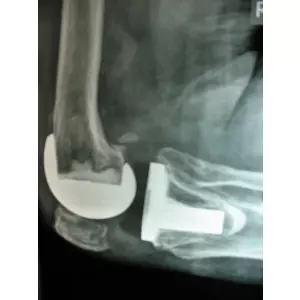

Ratibhai Patel

hip replacement surgery

Ratibhai Patel Details